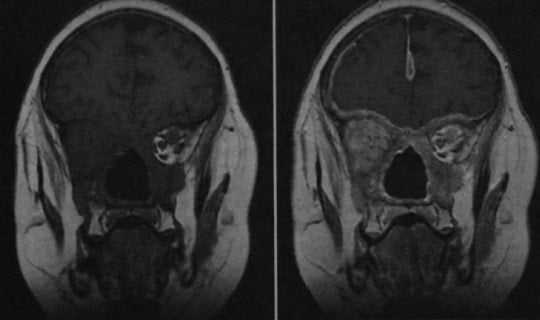

Гранулематоз Вегенера (МРТ) после хирургического вмешательства на придаточных пазухах. При контрастировании мягких тканей выявляется внутриглазничное и внутричерепное распространение гранулематозного процесса.

о Утолщение и контрастное усиление оболочек мозга

- Интракраниальные нарушения (поражение мозговых оболочек, инфаркты мозга)